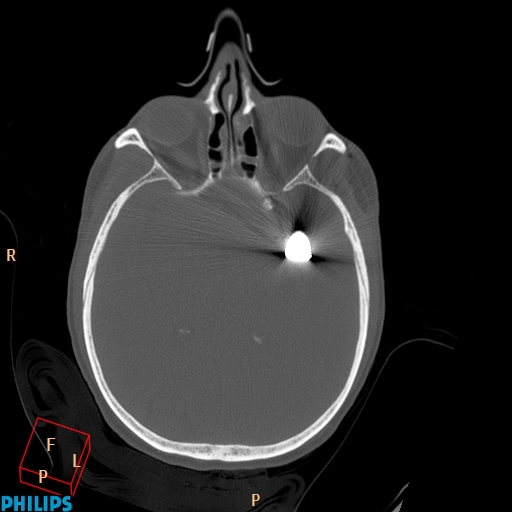

Accident de travail, chute sur une barre de fer. La barre de fer a été coupé sur le chantier pour dégager le patient A noter, comme on peut le voir sur la dernière image, que le patient était conscient et réveillé